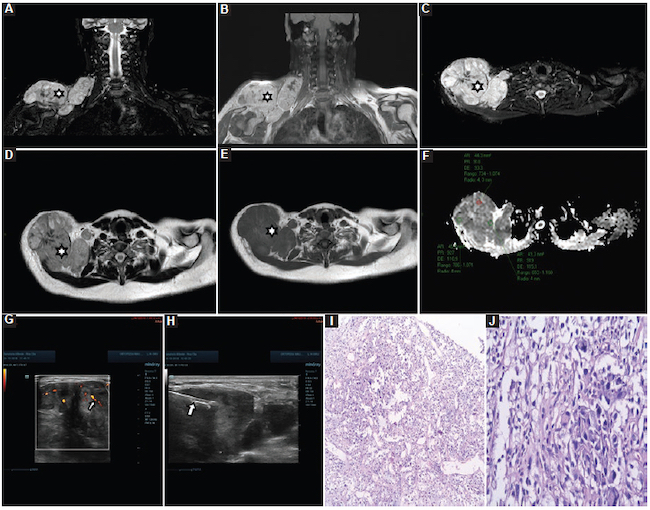

Linfomas: fueron siete casos, con un valor medio de CDA de 0,69 ± 0,19 × 10−3 mm2/s (0,50-1,00) (Fig. 15), de los cuales fueron cinco linfomas B, un linfoma del manto y un linfoma cutáneo.

Las muestras fueron analizadas por el anatomopatólogo mediante técnica de tinción simple con hematoxilina-eosina para realizar el diagnóstico de patología benigna o maligna (Fig. 4). Se informó el tipo de patología y se clasificaron las lesiones malignas determinando también el grado de infiltración.

Para las biopsias se utilizaron agujas dedicadas para cada tejido. Cuando las lesiones fueron de partes blandas se procedió con guía ecográfica con un equipo Mindray Resona 7 (Mindray Headquarter, Shenzhen, República Popular de China), con transductor de alta frecuencia, y se utilizaron agujas de corte tipo Tru-Cut de 14 o 16 G con una longitud de 10 cm (dependiendo del tamaño de la lesión), montadas en una pistola de disparo automático a doble armamento (Fig. 2). Cuando las lesiones fueron óseas se procedió con guía tomográfica con un equipo Siemens Somatom Sensation de 64 Canales (Alemania, Erlangen) y se utilizaron agujas de punción ósea para médula ósea de 11 × 4 G (Fig. 3).